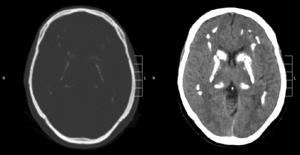

Idiopathic basal ganglia calcification, also known as Fahr disease, is a rare,[1] genetically dominant, inherited neurological disorder characterized by abnormal deposits of calcium in areas of the brain that control movement. Through the use of CT scans, calcifications are seen primarily in the basal ganglia and in other areas such as the cerebral cortex.[2]

Brain CT scan is the preferred method of localizing and assessing the extent of cerebral calcifications.

The calcification is usually identified on CT scan but may be visible on plain films of the skull.